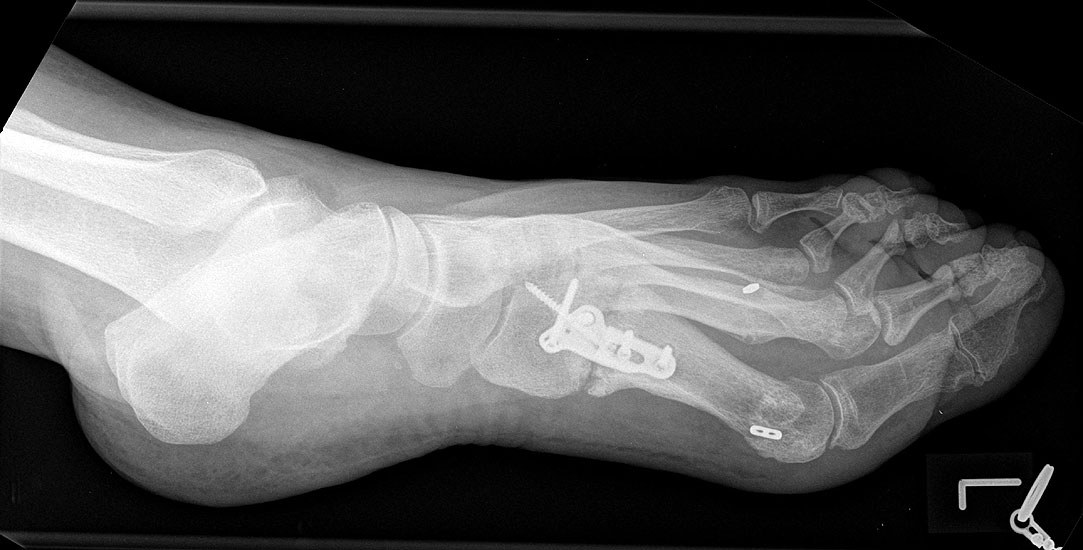

Die dorsoplantaren Röntgenaufnahmen zeigen eine Open-wedge Technik mit der normalerweise ein erhöhter intermetatarsaler Winkel gut zu korrigieren ist (Abbildung 3). Die Wirksamkeit einer Basisosteotomie ist umso größer, je proximaler diese durchgeführt wird. Je weiter distal die Osteotomie, umso geringer die Korrektur. Auf den postoperativen Bildern ist der distal unverändert große Abstand zwischen Metatarsale I und Metatarsale II erkennbar, bei gleichzeitiger Subluxation des Großzehengrundgelenks und dezentrierten Sesambeinen. Darüber hinaus finden sich initiale degenerative Veränderungen im Großzehengrundgelenk. Klinisch bestand eine hohe Weichteilspannung, bei verkürzter Extensor- und Flexor hallucis longus Sehne.  Daher wurde ein verkürzendes Verfahren zur Revision gewählt (Abbildung 4). Die Lapidusarthrodese stellt ein sehr zuverlässiges Verfahren zur Behandlung von Hallux valgus Rezidiven dar 9. Die Fusion des Tarsometatarsale-I-Gelenks kombiniert Stabilität mit einem hohen Korrekturpotenzial. Aufgrund der verfahrensimmanenten Verkürzung des ersten Strahls und der in diesem Fall bereits präoperativ vorhandenen Transfermetatarsalgie wurde die Entscheidung für eine verkürzte Weil-Osteotomie am zweiten bis fünften Strahl gefällt. Die Kombination beider Verfahren führte zu einem homogenen Metatarsale-Index und zu einer gleichmäßigen plantaren Druckverteilung 10. Die Hallux valgus interphalangeus Fehlstellung wurde mit einer Akin-Osteotomie korrigiert.